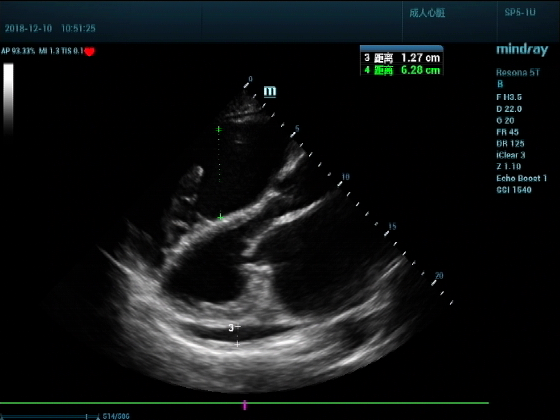

病例二:

男,81岁,全身浮肿来住院

超声可见:左房,右房,右室明显增大,主肺动脉及右肺动脉增宽,二尖瓣中度反流,三尖瓣重度反流,肺动脉轻度高压,心律不齐

心包积液盆腔积液。淤血性肝增大,肝静脉增宽。(右心衰声像改变)